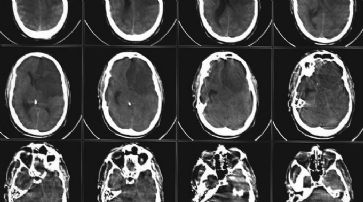

Nürnberg - Die Hirnrinde kann nach einem Schlaganfall keine neuen Nervenzellen bilden und damit Folgeschäden abmildern. Zu diesem Ergebnis kommen Forscher der Friedrich-Alexander-Universität Erlangen-Nürnberg.

Mit Hilfe der Radiokarbonmethode konnten sie in Kooperation mit einem schwedischen Team das Alter der Nervenzellen bestimmen. Sie stellten fest, dass die Zellen genau so alt waren wie der Patient selbst, also nicht in jüngerer Zeit neu gebildet worden waren.

«Der Schlaganfall stellt eine der häufigsten Todesursachen in der westlichen Welt dar, und nicht wenige der überlebenden Patienten sind im Alltag behindert oder pflegebedürftig», unterstreicht der Erlanger Hirnforscher Hagen Huttner, Mitarbeiter der Neurologischen Klinik am Universitätsklinikum der FAU. Die Experten widerlegen mit ihren in der Fachzeitschrift Nature Neuroscience veröffentlichten Ergebnissen bisherige Annahmen, dass die Hirnrinde - auch Kortex genannt - nach einem Schlaganfall selbst neue Nervenzellen bilden kann. Die Wissenschaftler machten sich für ihre Untersuchungen einen Nebeneffekt der mehr als 500 oberirdischen Atombombentests zu Zeiten des Kalten Krieges zunutze, bei denen ein radioaktives Kohlenstoff-Isotop vermehrt in der Atmosphäre freigesetzt und in die Erbsubstanz von Nervenzellen eingebaut wurde.

CCT-Untersuchung nach einem Schlaganfall. /

«Die Radiokarbonmethode wird beispielsweise in der Archäologie zur Altersdatierung von Fundstücken regelmässig eingesetzt», erläutert Huttner.

DNA-Isolierung als Schlüssel

Dem Forscher nach war Jahrtausende lang das Verhältnis von normalem und radioaktivem Kohlenstoff relativ konstant, so dass die Genauigkeit der Altersdatierung zu wünschen übrig liess. Durch die Atombombentests wurde das Kohlenstoffverhältnis drastisch verändert und gleicht sich - nach den Atomwaffensperrverträgen - über Jahrzehnte hinweg nun langsam wieder dem alten Niveau an. «Dadurch ist die zeitliche Auflösung der Radiokarbonmethode sehr genau geworden, und wir konnten sie für unsere präzisen wissenschaftlichen Untersuchungen zur etwaigen Neubildung von Nervenzellen nach einem Schlaganfall anwenden.» Die radiokarbonbasierten Altersdatierung nutzt den Umstand, dass der radioaktive Kohlenstoff über Pflanzen und Tiere in die Nahrungskette und folglich in den Menschen gelangte - und in der Folge auch bei jeder Neubildung von Zellen in deren Erbgut, und zwar in genau jenem Verhältnis zum normalen Kohlenstoff, wie es dem atmosphärischen Wert im Jahr der Geburt der Zelle entsprach. Wird die DNA aus Nervenzellen isoliert, die sich nach ihrer Entstehung nicht weiter teilen, und untersucht man das Kohlenstoff-Verhältnis, so lässt sich das Alter exakt datieren.